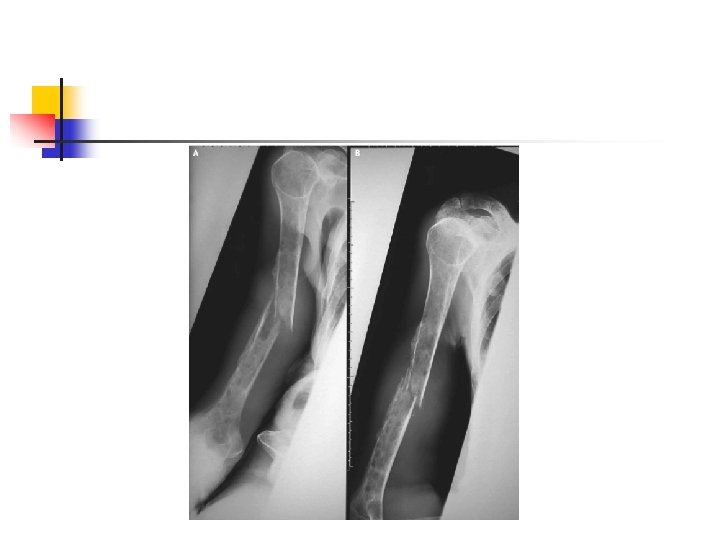

Multipl Myelom n n n Anemi Monoklonal protein (serum, idrar, her ikisi) Anormal kemik grafileri ve ağrı Hiperkalsemi Böbrek yetmezliği İle karakterize neoplastik plazma hücre hastalığıdır ABD de 100000 nüfusa yaklaşık 4. 5 vaka tanımlanmaktadır Erkek/Kadın: 1. 4

Bisfosfanatlar n n n Pirofosfatların sentetik analoglarıdır 1996 da alendronate osteoporoz tedavisi için onay aldı Osteoklast oluşumunu ve aktivasyonunu inhibe ederler

Bisfosfanatlar n n Osteoklastik kemik rezorbsiyonunu inhibe ederler Mandibula osteonekrozu n n Özellikle zoledronik asid kullanılanlarda Tolidomid + bisfosfonat kullanımında artmış risk